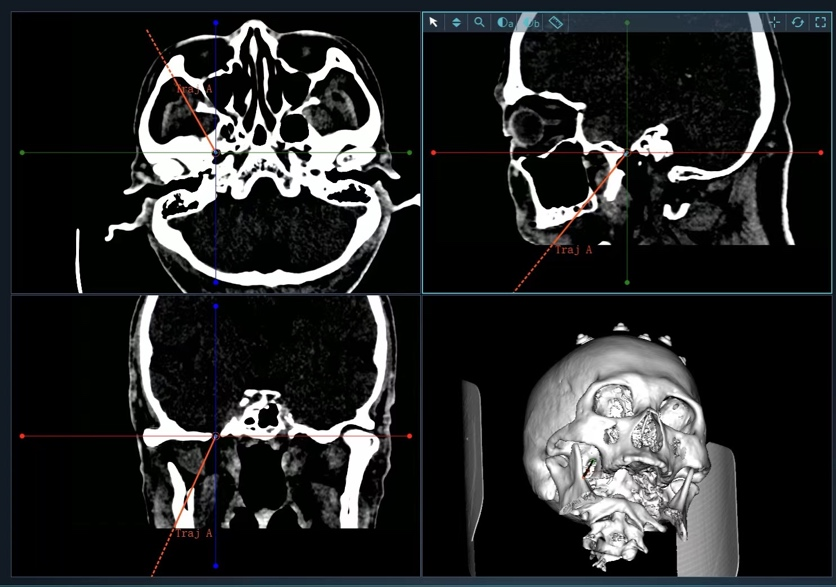

图1 术前通过机器人手术计划系统设计术中穿刺路径及靶点

但该患者手术需要精确的三维定位,术中需把穿刺针准确穿入皮下约8cm深、直径仅为3mm左右的卵圆孔,传统方法只能在C型臂引导下徒手穿刺,一次性穿刺成功率低。如何高效率穿刺成功,从而减少患者术中风险成为了迟令懿团队亟待解决的问题。在神经外科副主任李卫国的指导下,迟令懿采用机器人辅助立体定向下穿刺。术前验证误差仅为0.3mm,术中仅用10秒钟即完成了穿刺操作,避免了反复穿刺导致的血管、组织损伤,减少了C型臂透视的次数,降低了手术风险和并发症。术后,患者面部疼痛即刻消失,1天后顺利出院。